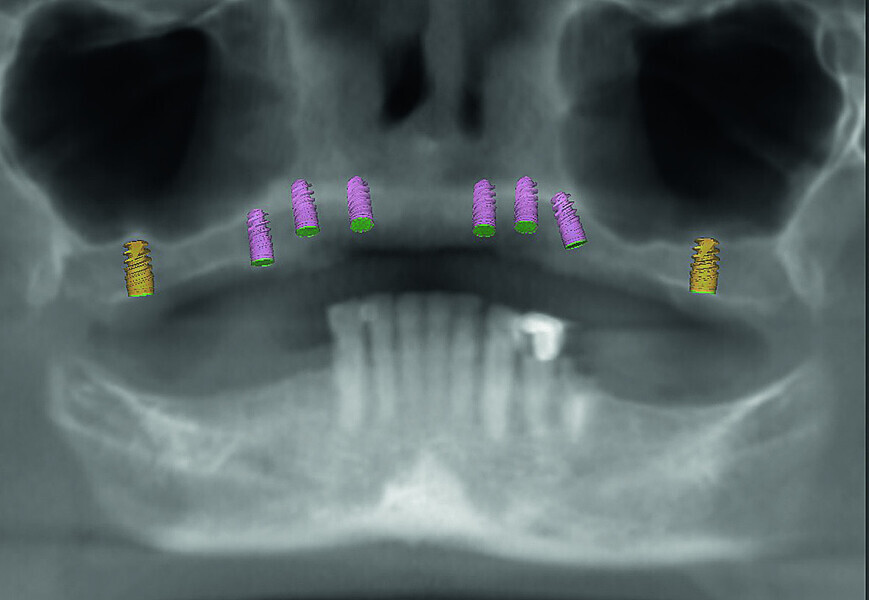

Fig. 5: Dentofacial analysis of proposed implants in maxillary arch.